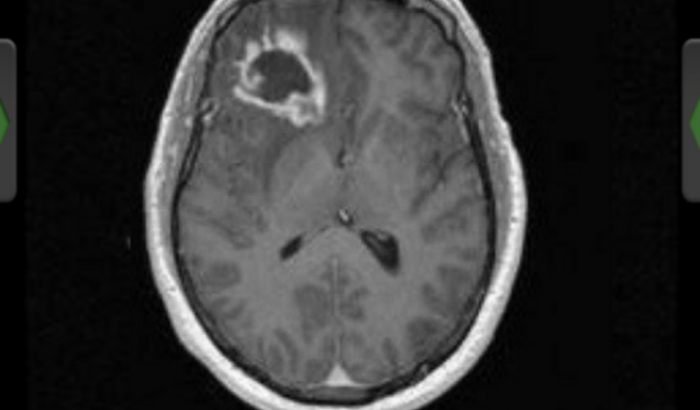

Ooooi gente , muitos me conhecem por ser uma pessoa muito alegre e espontânea , recentemente descobri que tenho um tumor benigno no meu lóbulo frontal que se for retirado agora existe 90% de chances de uma perca da visão atrapalhando também o comportamento , estou fazendo meu tratamento pelo meu convênio que foi des de quando comecei os exames e tratamentos , ele é um tumor sensível e que cresce rápido e estou fazendo uma vez por semana para tentarmos diminuir ele e está vaquinha e para pagar o meu tratamento com as rádios , exames e medicamentos, se sentirem no coração de doar qualquer valor será bem vindo , Deus abençoe a todos des de já 🙏🏼 cada pessoa que contribuir irá concorrer a dois jantares no restaurante ikigai Piracicaba 🍣🍱